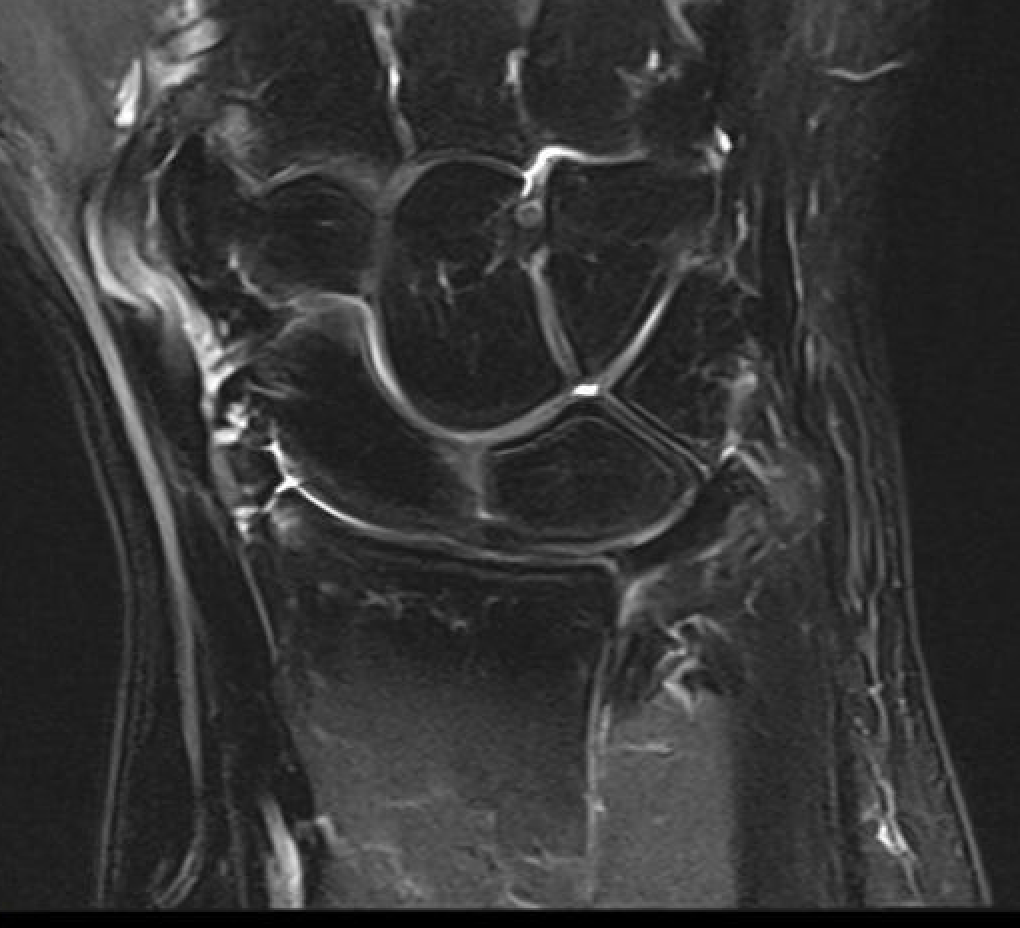

TFCC tears

Ulna sided tear

Radial sided TFCC tear

Central TFCC tear

Ulno-carpal abutment

Ulnocarpal abutment and lunate chondromalacia